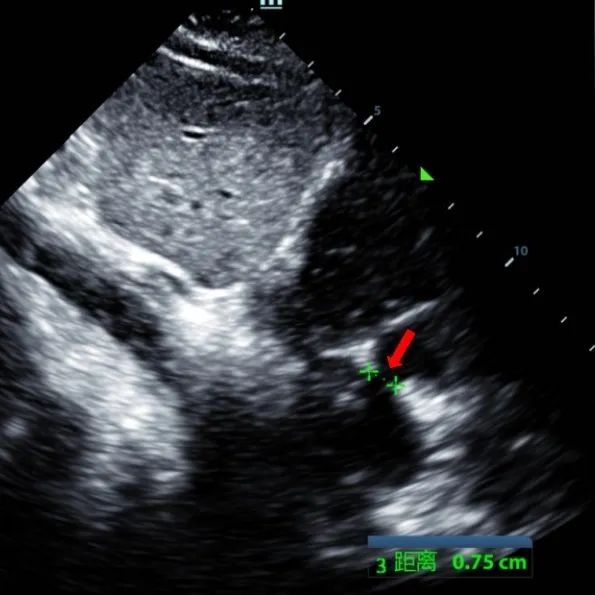

Um homem de 9 anos com ASD secundum (7,5-7,9mm) foi tratado usando um oclusor MemoSorb BDASD-I 12mm e sistema de entrega 12F. Não foram observadas complicações ou comorbidades pré-procedimento.

Serial echocardiographic follow-ups showed stable device position and favorable cardiac remodeling. Gradual degradation confirmed the occluder's long-term safety and efficacy.